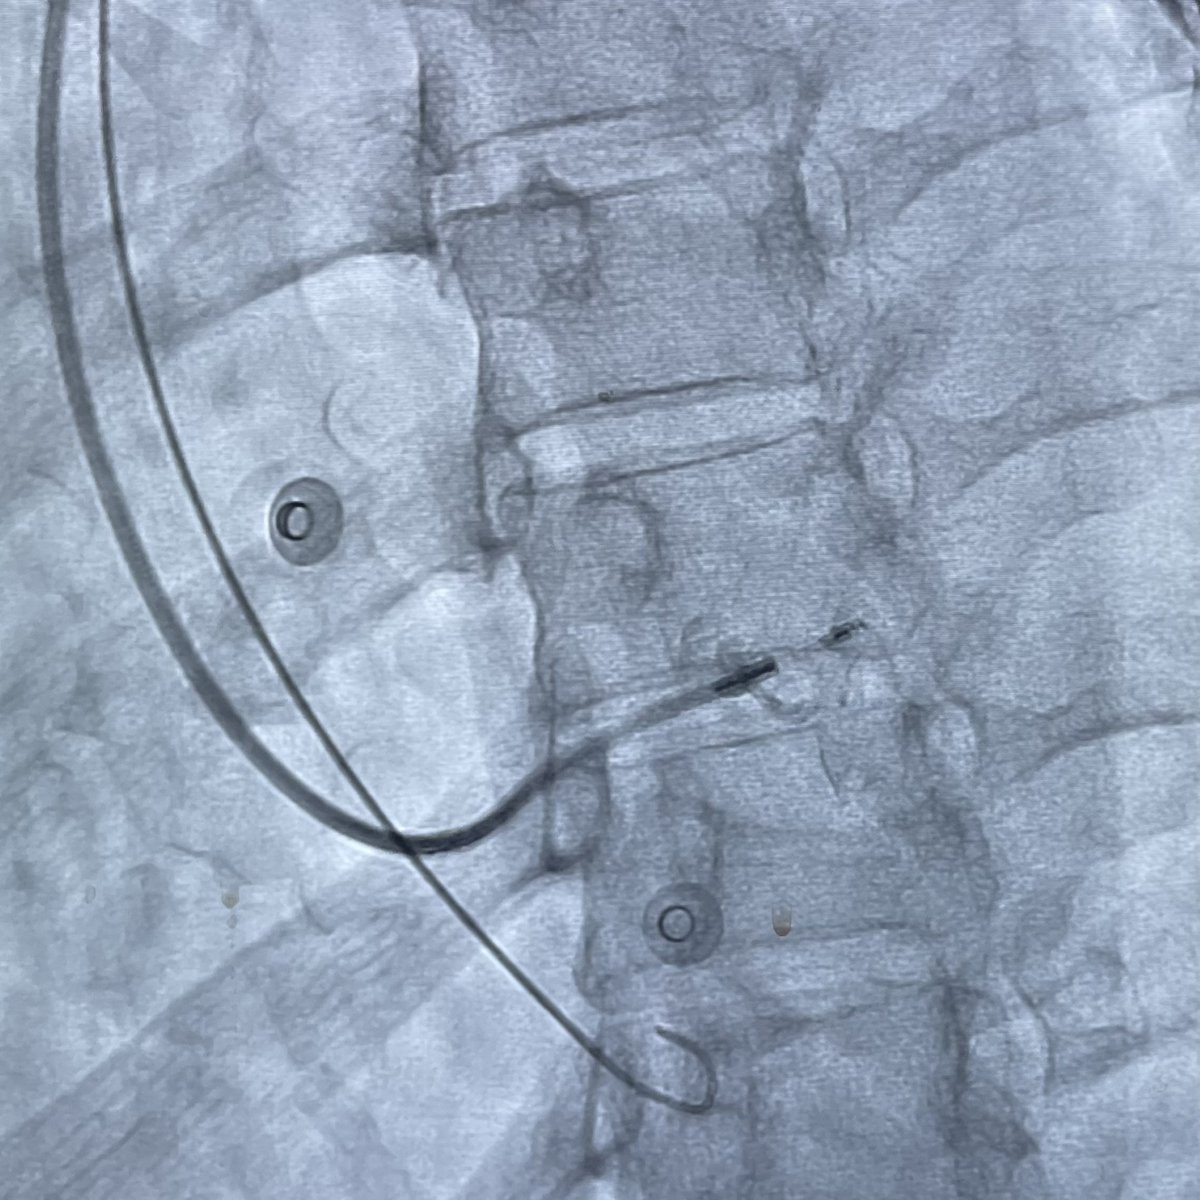

First left bundle branch area pacemaker (C315-HIS & 3830 system) with Pichmanil Khmao and John McFadden (rep) in Cambodia; from last week's Jeremiah’s Hope Clinic - Cambodia mission. Thank you Medtronic for device donations to help local EP teams learn skills to treat low-income patients. Sri Sundaram

First left bundle branch area pacemaker (C315-HIS &amp; 3830 system) with <a href="/pichmanil/">Pichmanil Khmao</a> and John McFadden (rep) in Cambodia; from last week's <a href="/JHMedMinistry/">Jeremiah’s Hope Clinic - Cambodia</a> mission. Thank you <a href="/Medtronic/">Medtronic</a> for device donations to help local EP teams learn skills to treat low-income patients. <a href="/srissundaram/">Sri Sundaram</a>